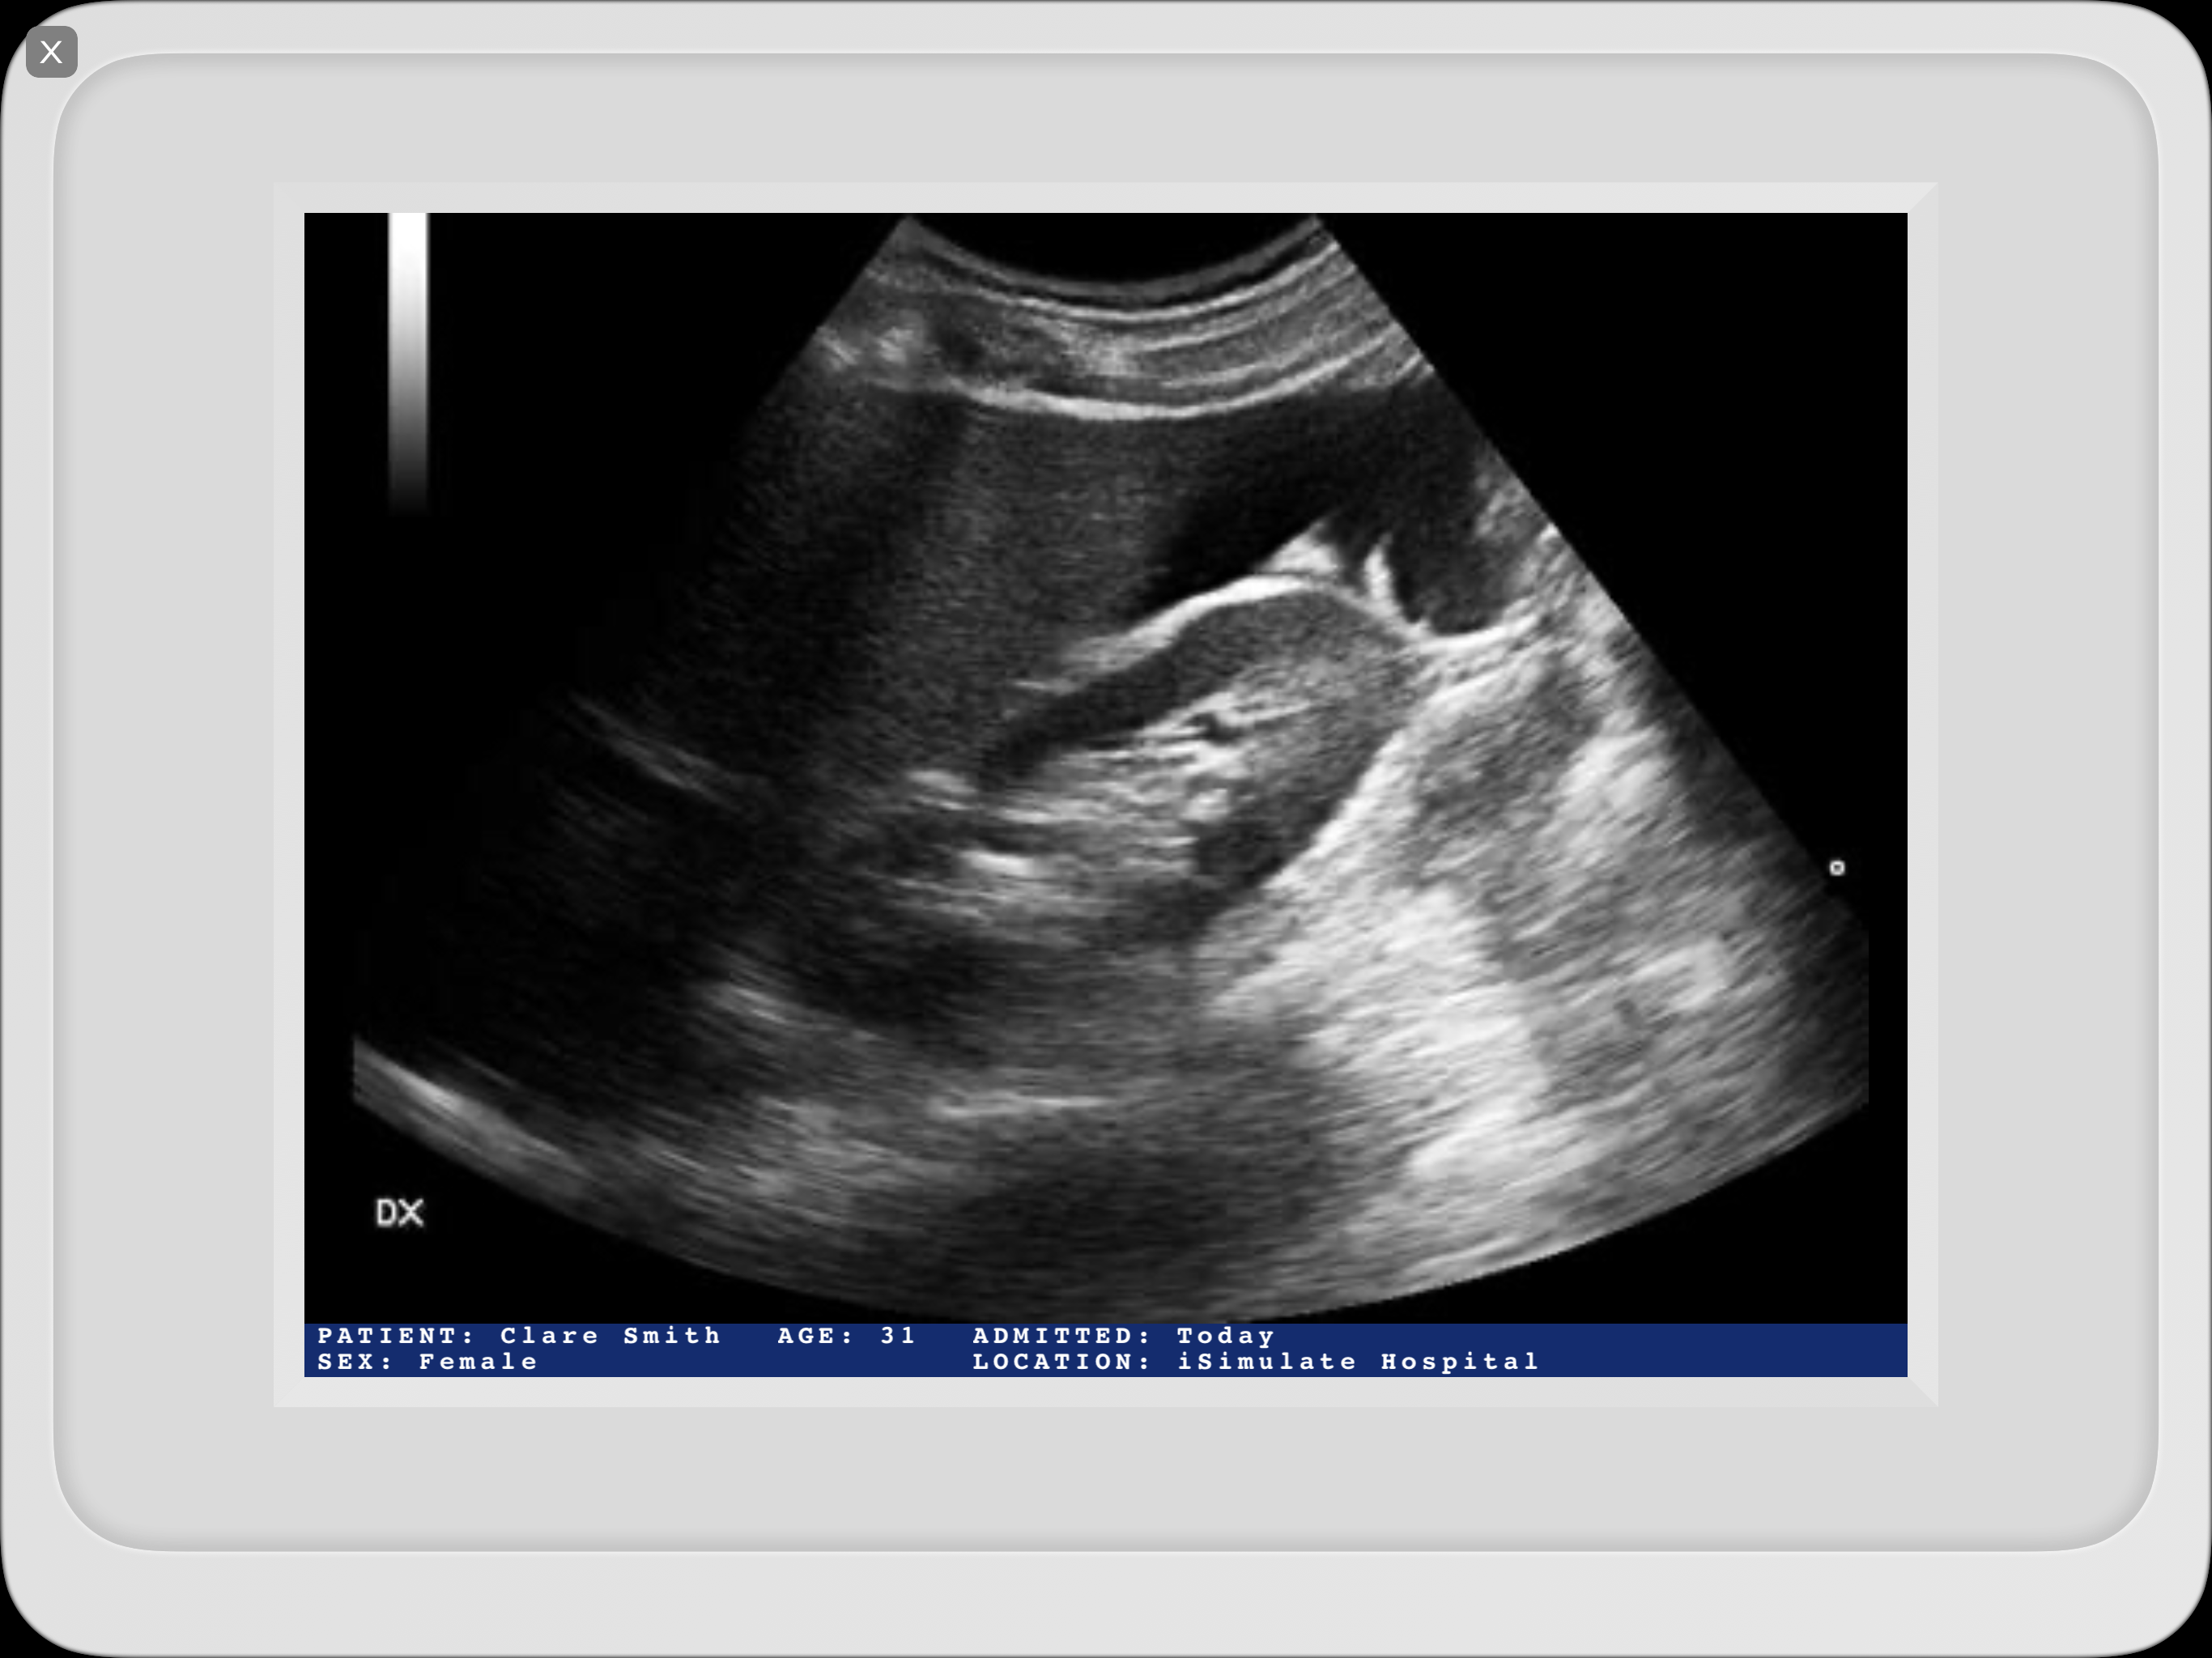

下の画像例のようにモニターへ表示される場合、Scenario Information(シナリオ情報)がメディア上にテキストで追加されます。

General(一般), Ultrasound(超音波), Radiography(X線撮影) 分類のメディアが対象です。

Ultrasound(超音波)